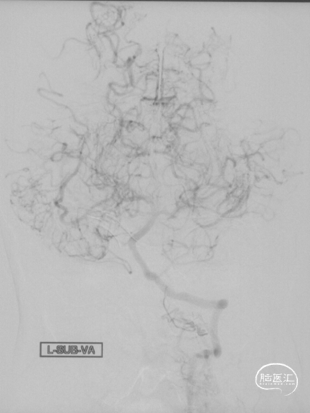

CTA和DSA

CTA和DSA所见:双侧颈内动脉闭塞,右侧椎动脉发出PICA后闭塞,左侧椎动脉V1-V2段闭塞。两条健壮的侧枝通过肌支吻合汇入左椎动脉V2段,构成了整个大脑大部分供血的主要来源。双侧颈外动脉亦有少量血流供应颅内。这样的颅内供血很容易发生失代偿,导致TIA甚至脑梗。